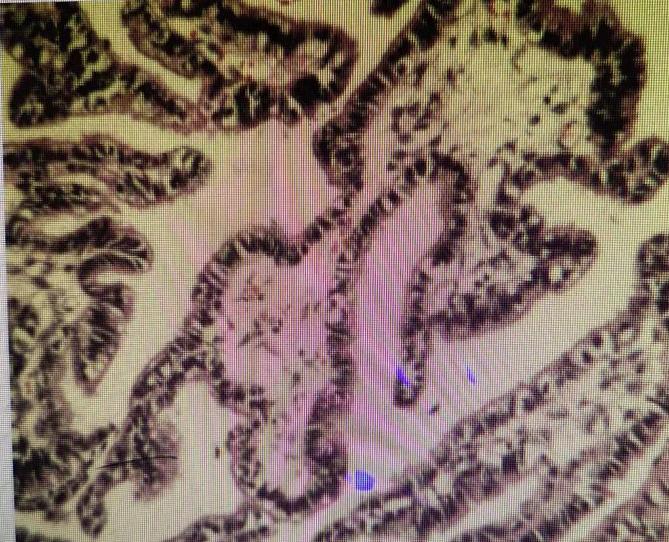

图为六六肿瘤切片病理图片